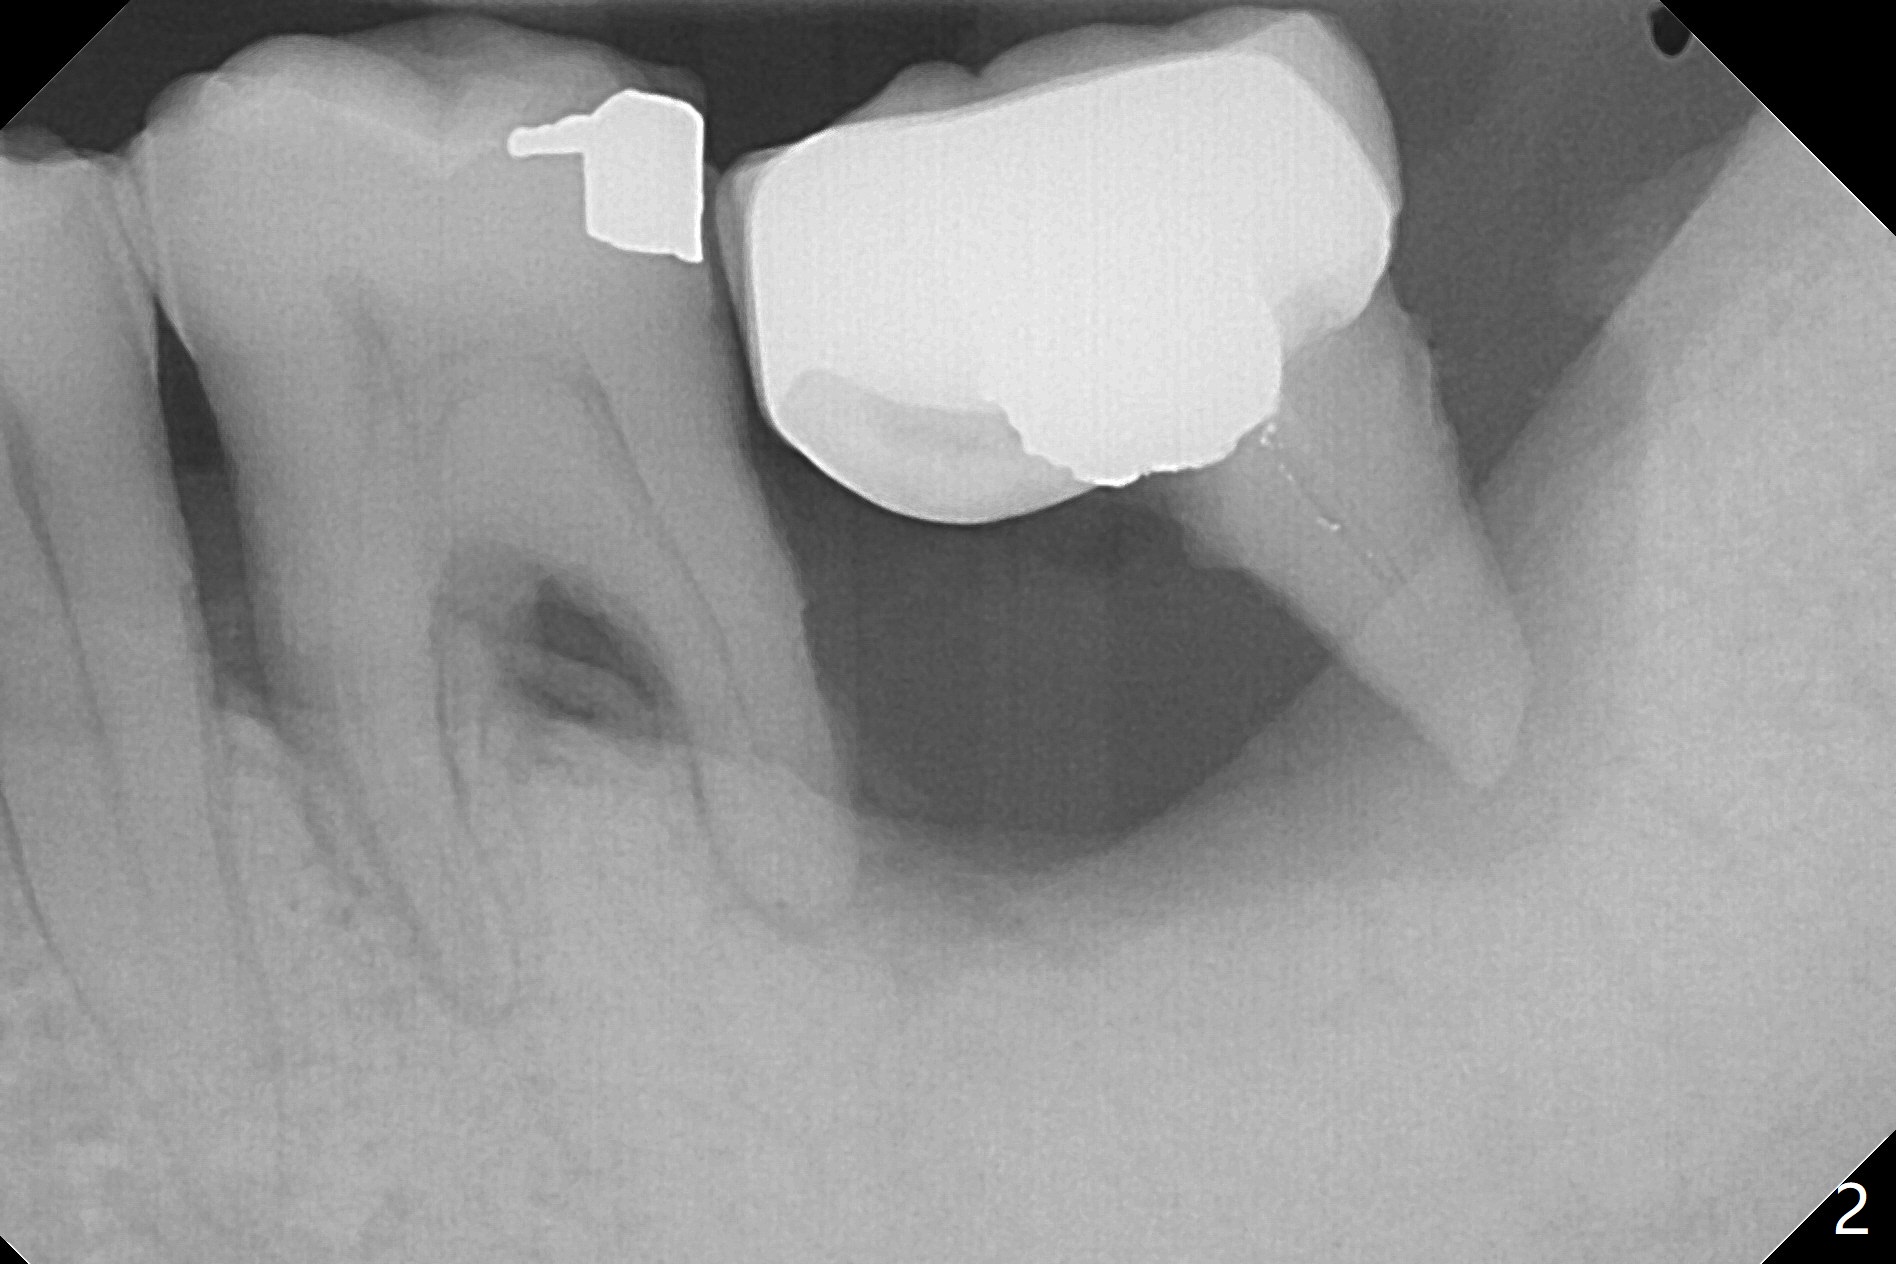

50岁男两年前不肯拔除左下7(图一),现在主动要求治疗(图二),需要做位点保留?怎么做的好?怎么收拾不动脑筋的惨剧(图三:仅远中牙槽窝植骨)?其实需要掀开近中粘骨膜(图四:箭头),然后植骨(红圆圈)。术后4.5个月近中缺损(图五:*),需要植牙植入很低(图六),离邻牙CEJ(<)很远。因此植体应该植入浅些(图七(CT矢状切面):箭头),离牙龈3毫米。放置袖3毫米(图八:粉红色)基台(紫色),然后在基台和植牙浅部植入粘性骨粉(图九:红圆圈)以及PRF膜(蓝线)。从冠状切面来看,颊侧(图十:B)需要多植骨,植牙前翻瓣(图十一:箭头),放置基台后(图十二),放置骨粉,膜,缝合。No Deviation 14 手术 Xin Wei, DDS, PhD, MS 1st edition 09/22/2020, last revision 03/02/2021